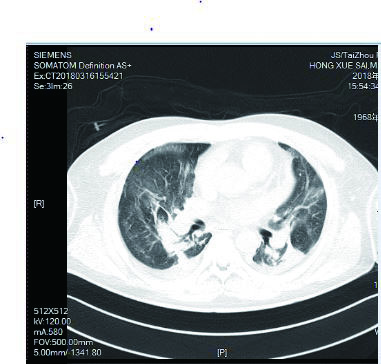

该患者入院后因氧合不能维持、呼吸窘迫直接从急诊收治ICU,大剂量激素冲击及气管插管,呼吸机SIMV+PS模式支持治疗,氧合指数改善不明显,及时行俯卧位通气,但氧合指数仍然小于100,PAO2 38 mmHg, SpO2 78%左右,考虑患者病情危重,且血流动力学不稳,血管活性药剂量大,当天下午行V-V模式ECMO治疗(右侧颈静脉-右侧股静脉),血流速度3.5 L/min,氧流量3.5 L/min,氧体积分数50%,行保护性机械通气,通气模式是压力控制(PC 15 cmH2O,PEEP 8 cmH2O,FiO2 50%,f 12次/min), 镇痛镇静,RASS评分在-4~-5分,必要时阿曲库铵静脉推注行肌肉松弛治疗。其他治疗:甲强龙500 mg治疗3 d,然后逐渐减量;乙酰半胱氨酸抗氧化、化痰、CRRT等支持治疗。ECMO治疗后生命体征明显改善,治疗第2天,血管活性药逐渐减量。治疗3 d后,循环稳定,停用血管活性药,床旁胸片提示:两肺弥漫渗出性改变,较前明显好转。患者症状好转,调节ECMO参数:血流速3 L/min,气体流速3 L/min,氧体积分数35%,控制SpO2 95%~100%之间。在ECMO治疗期间根据血流动力学和血气分析结果不断调整ECMO参数,在ECMO治疗5 d后,脱离ECMO,通气模式改为SIMV+PSV并过渡到PSV(PS 16 cmH2O,PEEP 5 cmH2O,FiO2 30%),氧合良好,在脱离ECMO 2 d后停呼吸机,停机1 d后拔除气管插管。行胸部CT检查示:两肺散在炎性病变,双侧胸膜腔积液(图 3),床旁胸片提示两肺炎性病变(图 4),两肺弥漫性渗出明显改善。后经1周治疗,查胸部CT示:右肺中下叶及左肺少许慢性炎性改变(图 5),病情稳定转至呼吸科病房。

| 图 3 3月16日胸部CT |